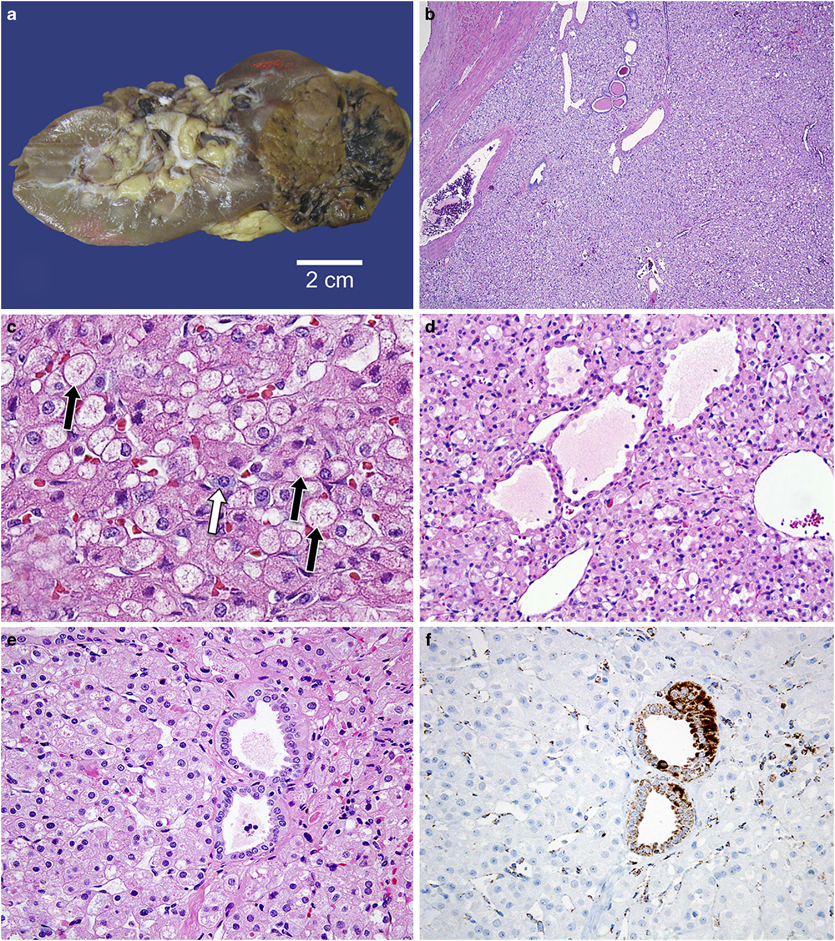

RENAL ONCOCYTOMA

- Gross:

- Circumscribed, not encapsulated

- Mahogany brown, central scar

- No gross necrosis

- Micro:

- Tight nests and alveoli surrounded by myxoid or hyalinized hypocellular stroma

- Diffuse, granular eosinophilic cytoplasm

- Uniformly rounded nuclear contours

- No frequent/atypical mitoses, sheets, sarcomatoid

- Perinephric fat involvement permissible if the above histologic criteria are satisfied

- Positive stains:

- CD117

- Negative stains:

- CK7

CHROMOPHOBE RCC

- Gross:

- Presents as a cortical neoplasm, classically mahogany brown in color

- MIcro:

- Solid, sheet-like growth pattern

- Clear to eosinophilic cytoplasm with perinuclear halos

- Plant-like cell membrane

- Raisinoid nuclear contours

- Positive Stains

- CK7

- CD117

- Hale colloidal iron

- AE1/AE3

- Negative Stains

- Vimentin

- Carbonic anhydrase IX

- Birt Hogg Dube syndrom: chromophobe/oncocytoma